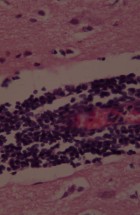

The Department’s main activities encompass research and specialized tasks. It focuses on clinical, pathoanatomical, pathohistological, immunohistochemical, and molecular diagnostics of diseases in both domestic and wild animals, including reproductive pathology. Operations within the department are structured around fieldwork and laboratory analyses.

- Performing pathohistological, cytological, immunohistochemical, and molecular diagnostics.